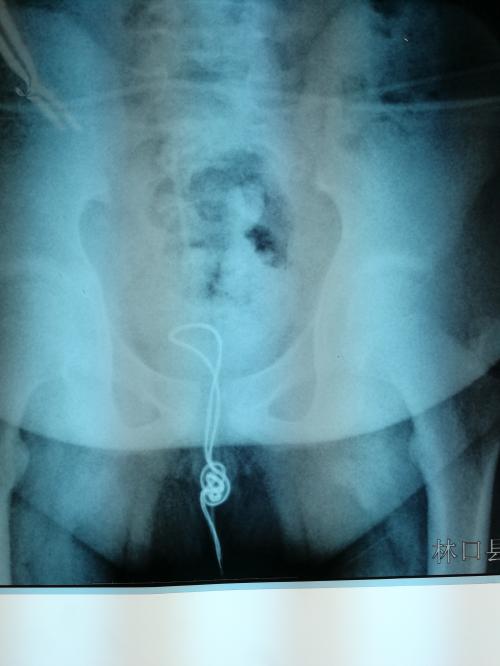

次日一早,小明的父母带他来到哈市儿童医院,拍片结果显示,一根10厘米左右的线盘在膀胱内,已经有了炎症,最可怕的是线在膀胱内已经打结,一旦将线强行拉出就会损伤尿道壁导致二次伤害。医生将尿道切开2厘米的小口,将异物取出,手术非常顺利。